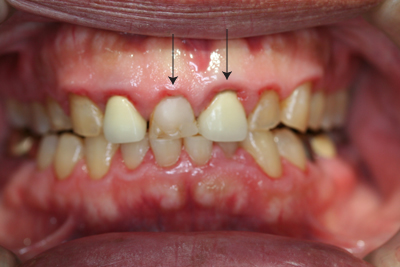

▼歯磨き指導だけで改善した例です。

治療前

治療後

▼歯磨き指導で症状が安定しました。

治療前

治療後

歯の動揺と隙間が広くなってきた事を気にされて来院されました。

治療:左下奥歯(臼歯)は欠損したままになっておりましたのでインプラントによる欠損部の治療を行いました。欠損部にインプラントを入れるだけの十分な骨量がありませんでしたが、残存歯の負担をなるべく少なくするため、インプラント治療をおこなっています。その他歯周病治療を行っておりますが、上顎正中は歯槽骨の欠損が大きかった為、E・M・D(エムドゲイン)により再生治療も行っています。

治療前

治療後